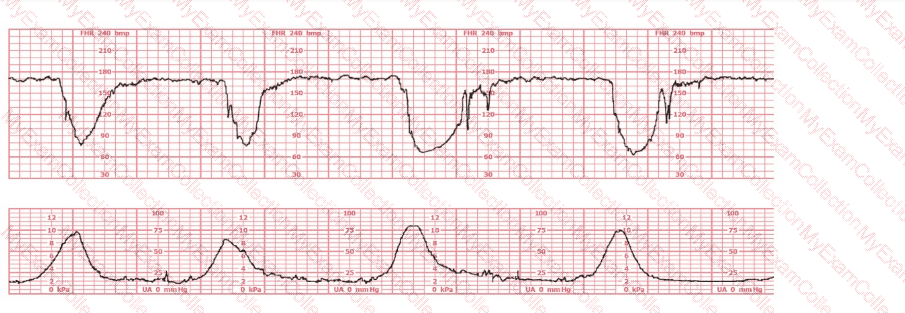

A woman has been 5 cm dilated for the past 3 hours. The tracing shown has developed over the last 30 minutes. The best initial course of action is to: